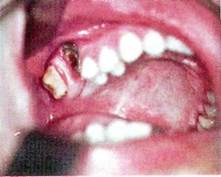

Рак верхней челюсти

Клиника зависит от локализа­ции исходного очага опухоли. При развитии рака из слизистой обо­лочки неба, щеки или альвеолярного отростка верхней челюсти опре­деляется вначале характерная клиническая картина рака слизистой оболочки рта, а затем, по мере разрушения кости, процесс становится все более распространенным, появляется подвижность зубов, затруд­ненное носовое дыхание, ограничивается открывание рта. Затем, про­растая верхнечелюстную пазуху, рак дает одинаковую клиническую картину с распространенным поражением, развивающимся из слизи­стой оболочки пазухи. Клиника рака верхнечелюстной пазухи в начальной стадии заболе­вания мало характерна и сходна с хроническим гайморитом: боли, как правило, в этот период отсутствуют, отмечается серозное отделя­емое из носового хода и заложенность носа. Такая картина может на­блюдаться в течение 2-4 месяцев, не беспокоя особенно больных. По­степенно процесс прогрессирует, присоединяется чувство тяжести в верхней челюсти соответствующей стороны, появляются гнойно-сук­ровичные выделения из носа и многие другие симптомы, возникнове­ние которых связано с исходной локализацией опухоли в том или ином участке верхнечелюстной пазухи. Для определения места пора­жения и направления роста опухоли используют схему Онгрена, деления верхнечелюстной пазухи на сегменты. Первая наклонная плоскость, идущая от внутреннего орбитального края к углу нижней челюсти, образует два отдела пазухи — нижне­передний и верхнезадний. Вторая сагиттальная плоскость, являющая­ся перпендикуляром к зрачковой линии, делит каждый из отделов на внутренний и наружный. Таким образом, образуется четыре сегмента: нижнепередний внутренний, нижнепередний наружный, верхнезад­ний внутренний и верхнезадний наружный.

Для опухоли, локализующейся в нижнепереднем внутреннем сег­менте верхнечелюстной пазухи, характерным является подвижность малых коренных зубов и клыка с явлениями парестезии. После удале­ния их из лунки начинает выбухать опухолевая ткань. Отмечается так­же заложенность соответствующего носового хода за счет распростра­нения опухоли в полость носа. При прорастании передней стенки и мягких тканей появляется деформация лица. Поражение нижнепе­реднего наружного сегмента ведет к разрушению бугра, расшатыва­ются и располагаются как бы "в вате" верхние большие коренные зубы. Опухоль может распространяться на ветвь нижней челюсти, область миндалины и, прорастая жевательные мышцы, вызывать ограничение открывания рта. Рак верхнезаднего внутреннего сегмента распростра­няется преимущественно в сторону решетчатого лабиринта и глазни­цы, возникает смещение глазного яблока и экзофтальм. Часто отмеча­ется головная боль и парестезия кожи соответственно иннервации 2-й ветви тройничного нерва. Развитие опухоли в верхнезаднем наруж­ном сегменте приводит к экзофтальму с явлениями диплопии, суже­нию глазной щели. Наблюдается сильная боль в зоне иннервации нижнеглазничного нерва. Опухоль прорастает в крылонебную ямку. В случае распространенного поражения, когда вовлечена вся верхне­челюстная кость, клиническая картина опухоли многообразна и вклю­чает симптомы, характерные для поражения всех отделов пазухи.